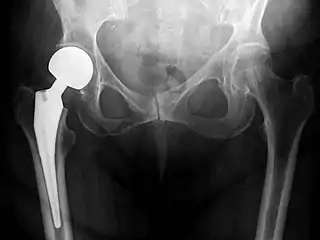

An X-ray showing a left hip (right of image) that has been replaced, with the ball of this ball-and-socket joint replaced by a metal head that is set in the femur and the socket replaced by a cup

Post-operative projectional radiography is routinely performed to ensure proper configuration of hip prostheses.